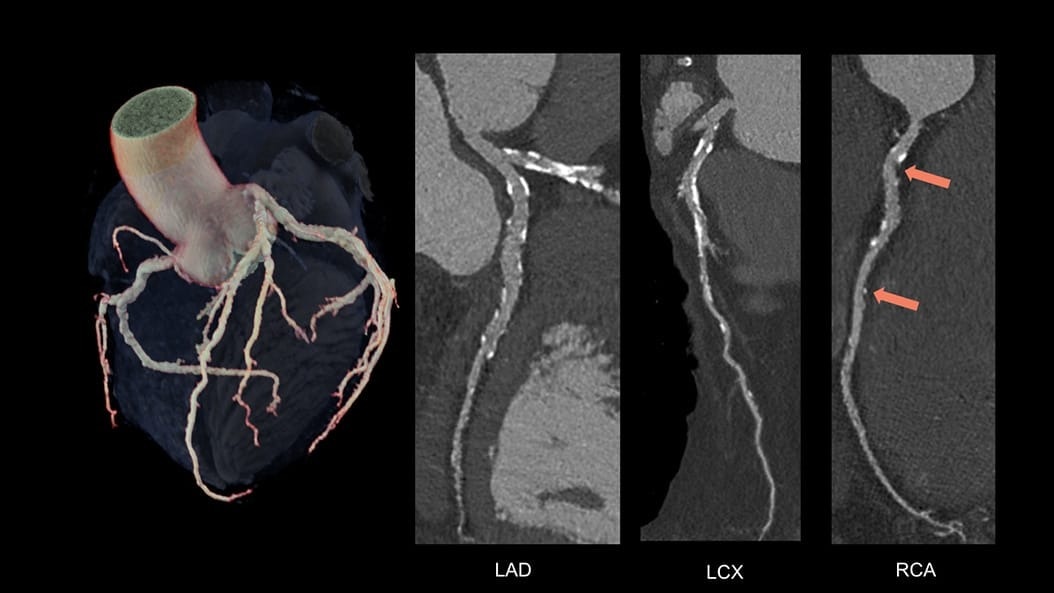

Expect exceptional results routinely—in a single beat

Complex CCTA becomes routine when advanced AI supports every image—streamlining and standardizing workflows even for challenging patients with unreliable ECG traces. See how Radiomed transformed its cardiac CT program to consistently deliver exceptional results.

CardiQ Suite

An integrated suite of CT Cardiac post-processing tools, built for automation and workflow efficiency.